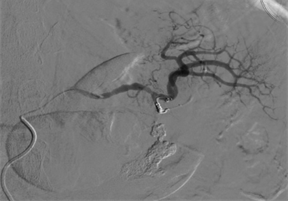

The patient was hemodynamically stable, but with mild tachycardia. He underwent endovascular embolization treatment, in which he was selectively catheterized in the splenic artery and dorsal pancreas (Figure 2). Lipiodol and a controlled-release spring were used to occlude the pseudoaneurysm and dorsal pancreatic artery, maintaining patency of the splenic artery (Figures 3 & 4). At the end of the procedure, there was no extravasation of contrast. During hospitalization, the patient remained in an intensive care bed for 48 hours for hemodynamic surveillance and clinical treatment of post-contrast acute renal failure. The patient was discharged 96 hours after the procedure. Being guided at every hospital discharge to follow up in the outpatient service.

Because it is a rare complication, there are few cases described in the literature showing the diagnosis and management of the condition. In our case, there was therapeutic success through endovascular treatment with glue and controlled-release coils. Thus, the patient was spared an open surgical procedure, prolonged hospitalization and possible intraoperative complications of hostile anatomy due to the history of recurrent pancreatitis. In addition, the patency of his splenic artery was maintained without the use of a stent and consequently maintenance of the spleen.

The endovascular approach in the treatment of pseudoaneurysm of the dorsal artery of the pancreas is safe and effective, especially when the diagnosis and treatment occur early.